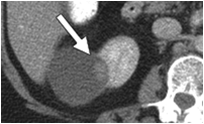

![]() |

| Cystic renal cell carcinoma ( with mural nodule). |